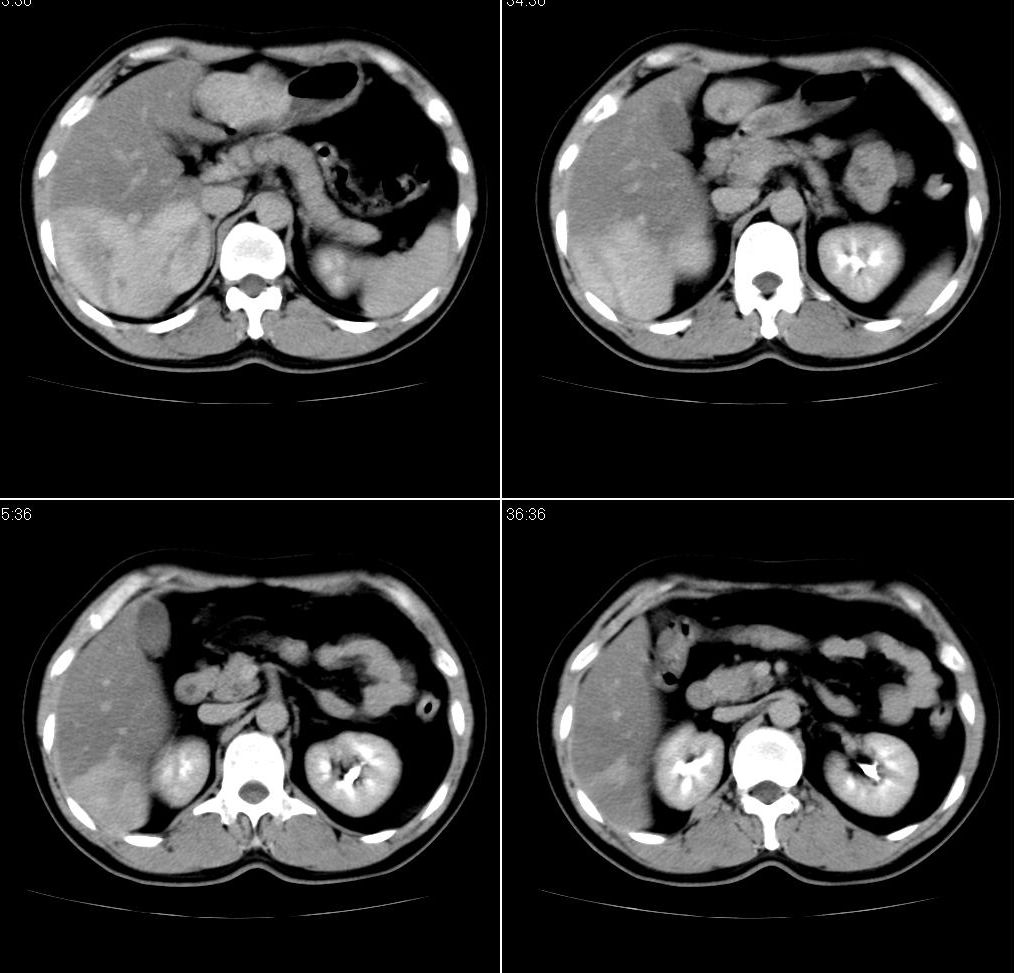

男,43岁。体检发现肝脏病变

肝右叶密度均匀减低,左叶增大,表面凹凸不平,内有低密度影。脾不大其密度较肝稍高。考虑1脂肪肝2肝左叶占位。建议增强。

肝右叶密度均匀减低,左叶增大,表面凹凸不平,内有低密度影。考虑1局灶性脂肪肝 2肝左叶占位。建议增强。

增强后诊断很明确了,缓慢结节样强化:肝内多发血管瘤

从这个病例可以看出增强ct优势何其重要性和必要性。